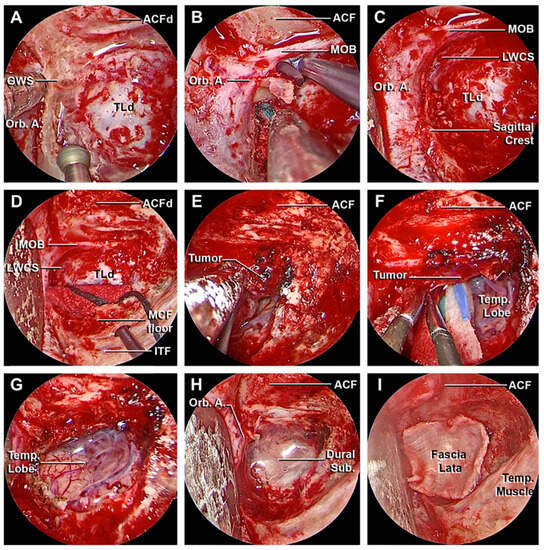

3.1. Step-by-Step Dissection

3.1.1. Craniectomy

3.1.2. Access to the Middle Fossa and Petrous Apex

3.1.3. Access to the Lateral Wall of the Cavernous Sinus and Anterior Clinoidectomy